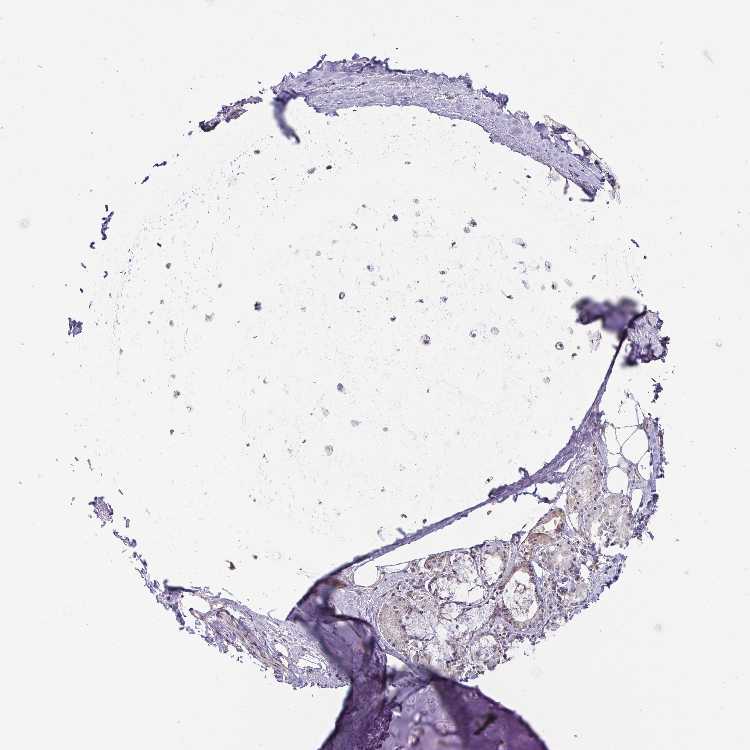

SOFT TISSUE 1 - Antibody stainingi

Antibody staining in the annotated cell types in the current human tissue is reported as not detected, low, medium, or high, based on conventional immunohistochemistry profiling in selected tissues. This score is based on the combination of the staining intensity and fraction of stained cells.

Each image is clickable and will lead to virtual microscopy that enables deeper exploration of all samples and also displays staining intensity scores, fraction scores and subcellular localization as well as patient and tissue information for each sample.

Antibody HPA041802Antibody HPA054532

Chondrocytes MediumNot detected

Fibroblasts MediumNot detected

Peripheral nerve -Not detected

SOFT TISSUE 2 - Antibody stainingi

Chondrocytes Medium-

Fibroblasts HighNot detected